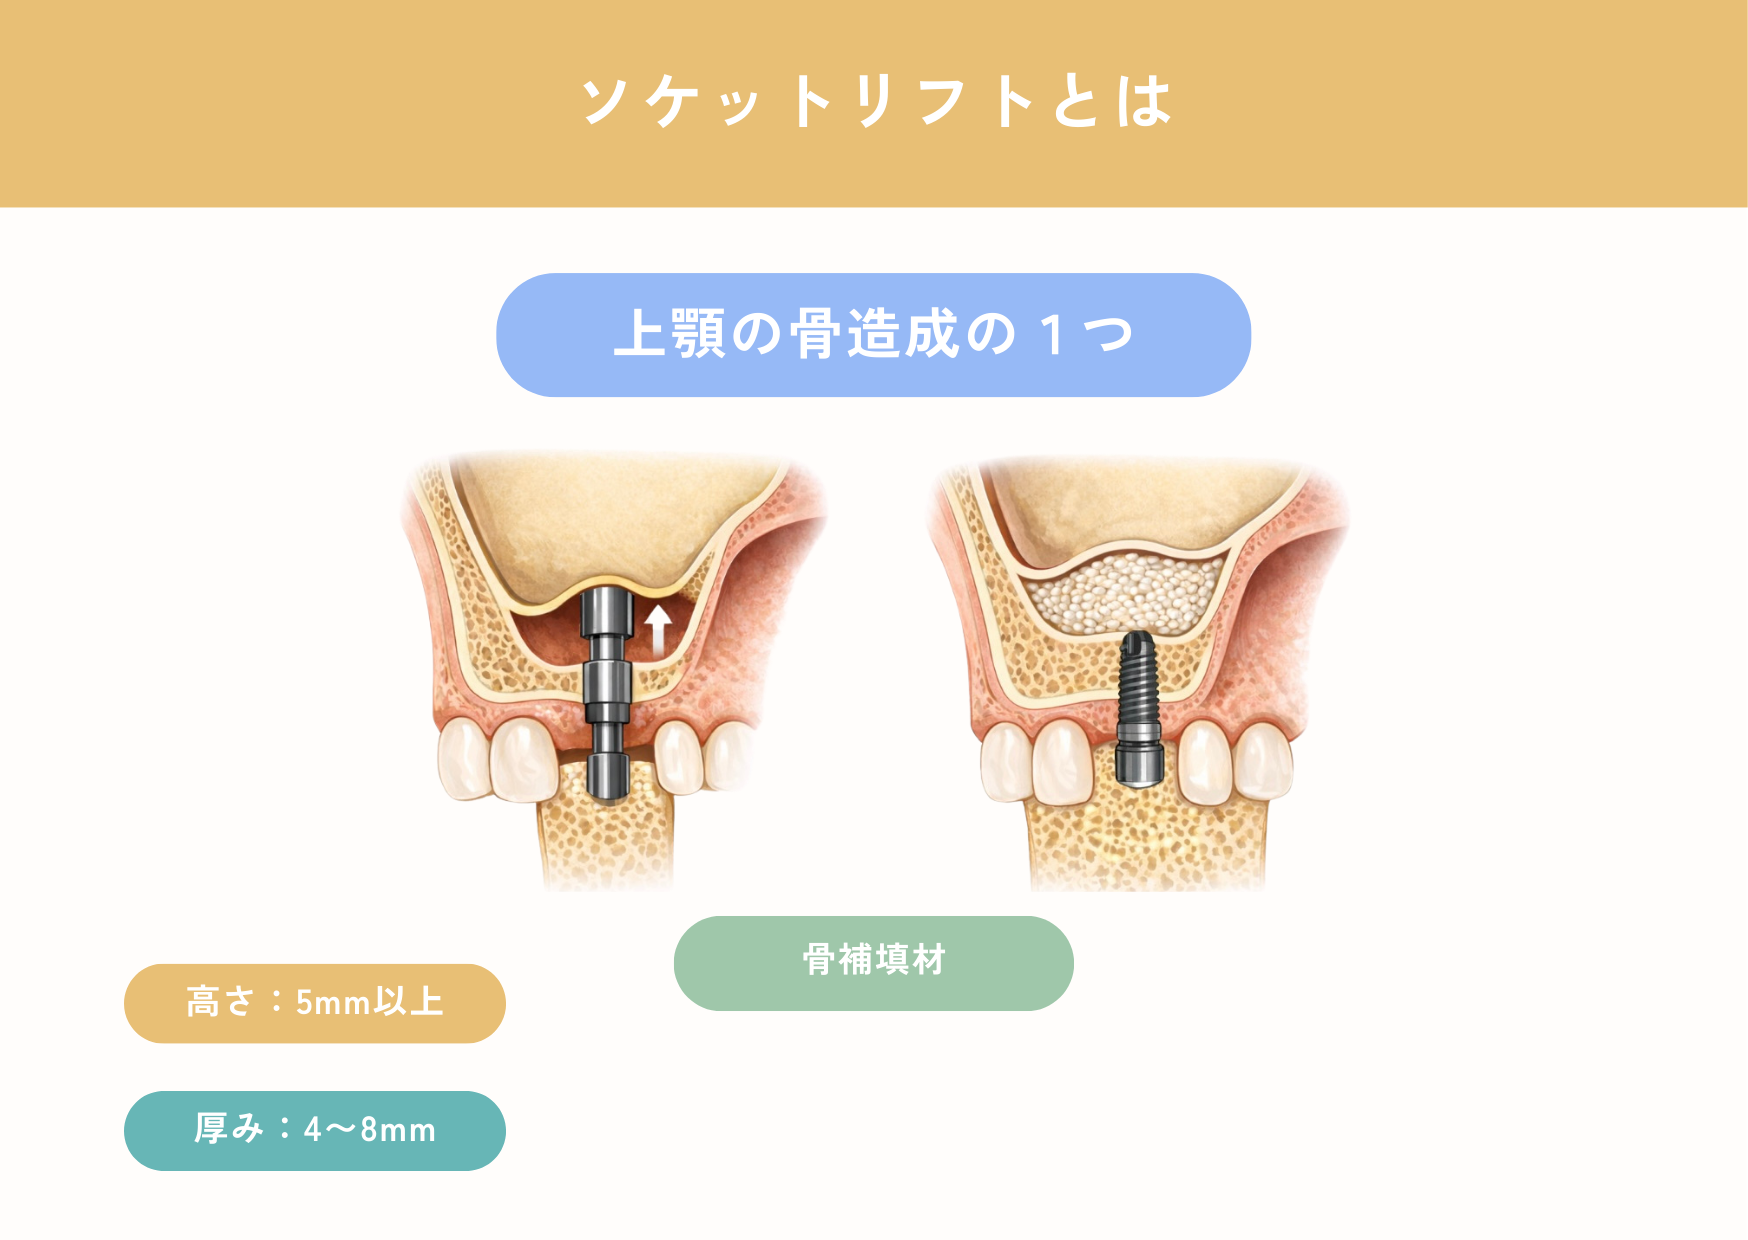

まず、ご紹介するのは骨の高さが「あと少しだけ足りない」という場合に選ばれるソケットリフトという方法です。上顎のインプラント治療では、鼻の横にある「上顎洞」との距離が重要になります。

2-1 ソケットリフトの仕組み

ソケットリフトは、インプラントを埋め込むためにあける「小さな穴」をそのまま利用しています。歯茎を大きく切除することはなく、その穴から専用の器具を入れ、上顎洞の底にある薄い粘膜(シュナイダー膜)をトントンと少しずつ、丁寧に押し上げていきます。粘膜を無理に引っ張るのではなく、持ち上げるイメージで操作するため、組織へのダメージが少ないのが特徴です。そして、持ち上げてできたスペースに、骨の代わりとなる材料を入れ、その上にインプラントを埋入していきます。

2-2 誰に向いている?

ソケットリフトは、すべての方に適応しているわけではありませんが、次のような条件に当てはまる方には非常に適した治療方法となります。

・インプラントを入れる部位に骨の厚みが5mm以上残っている方

・できるだけ手術回数を少なくし、1回で治療を終えたい方

・外科処置に対する不安が強く、痛みや腫れをできるだけ抑えたい方

・お仕事や日常生活への影響を最小限にしたい方

CT検査で骨の状態を正確に確認したうえで、「ソケットリフトで安全に行える」と判断された場合に選択されます。